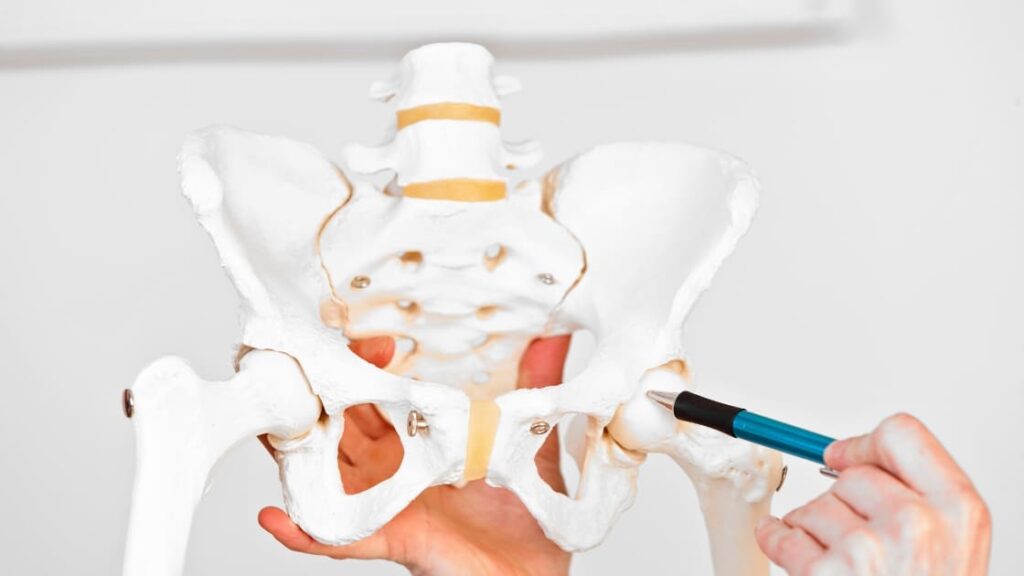

A lesão do labrum do quadril é uma condição ortopédica que afeta a cartilagem que reveste a borda do encaixe da articulação do quadril, chamada de labrum acetabular. Essa estrutura tem a função de estabilizar e amortecer os movimentos da cabeça do fêmur dentro da cavidade acetabular. Quando ocorre uma lesão, o paciente pode experimentar dor, desconforto e limitação de movimentos, impactando diretamente sua qualidade de vida.

Essa lesão pode acontecer por diferentes motivos. As causas mais comuns envolvem movimentos repetitivos, alterações anatômicas no quadril (como o impacto femoroacetabular), traumas diretos ou torções súbitas durante atividades físicas. Dançarinos, atletas, praticantes de artes marciais e pessoas que fazem exercícios de alto impacto estão entre os grupos mais suscetíveis.

O diagnóstico é feito por meio de avaliação clínica com ortopedista especializado e exames de imagem. A ressonância magnética com contraste (artro-RM) é o exame mais indicado, pois permite visualizar com clareza as estruturas internas do quadril e identificar a extensão da lesão no labrum.